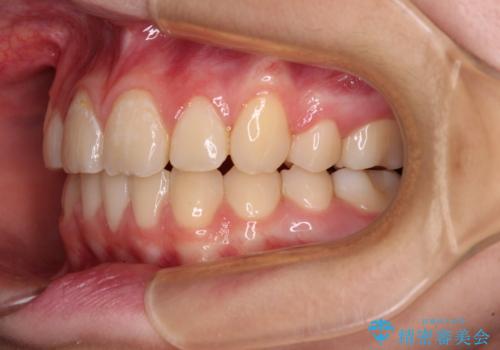

まずは補助装置を用いて八重歯を改善し、インビザラインにて歯列を整えましたが、当初の懸念が的中し、臼歯部の咬合を安定させることができませんでした。

海外留学の予定もあったため、後半は上下ワイヤー装置にて矯正治療を継続し、違和感なく咬合させることとなりました。